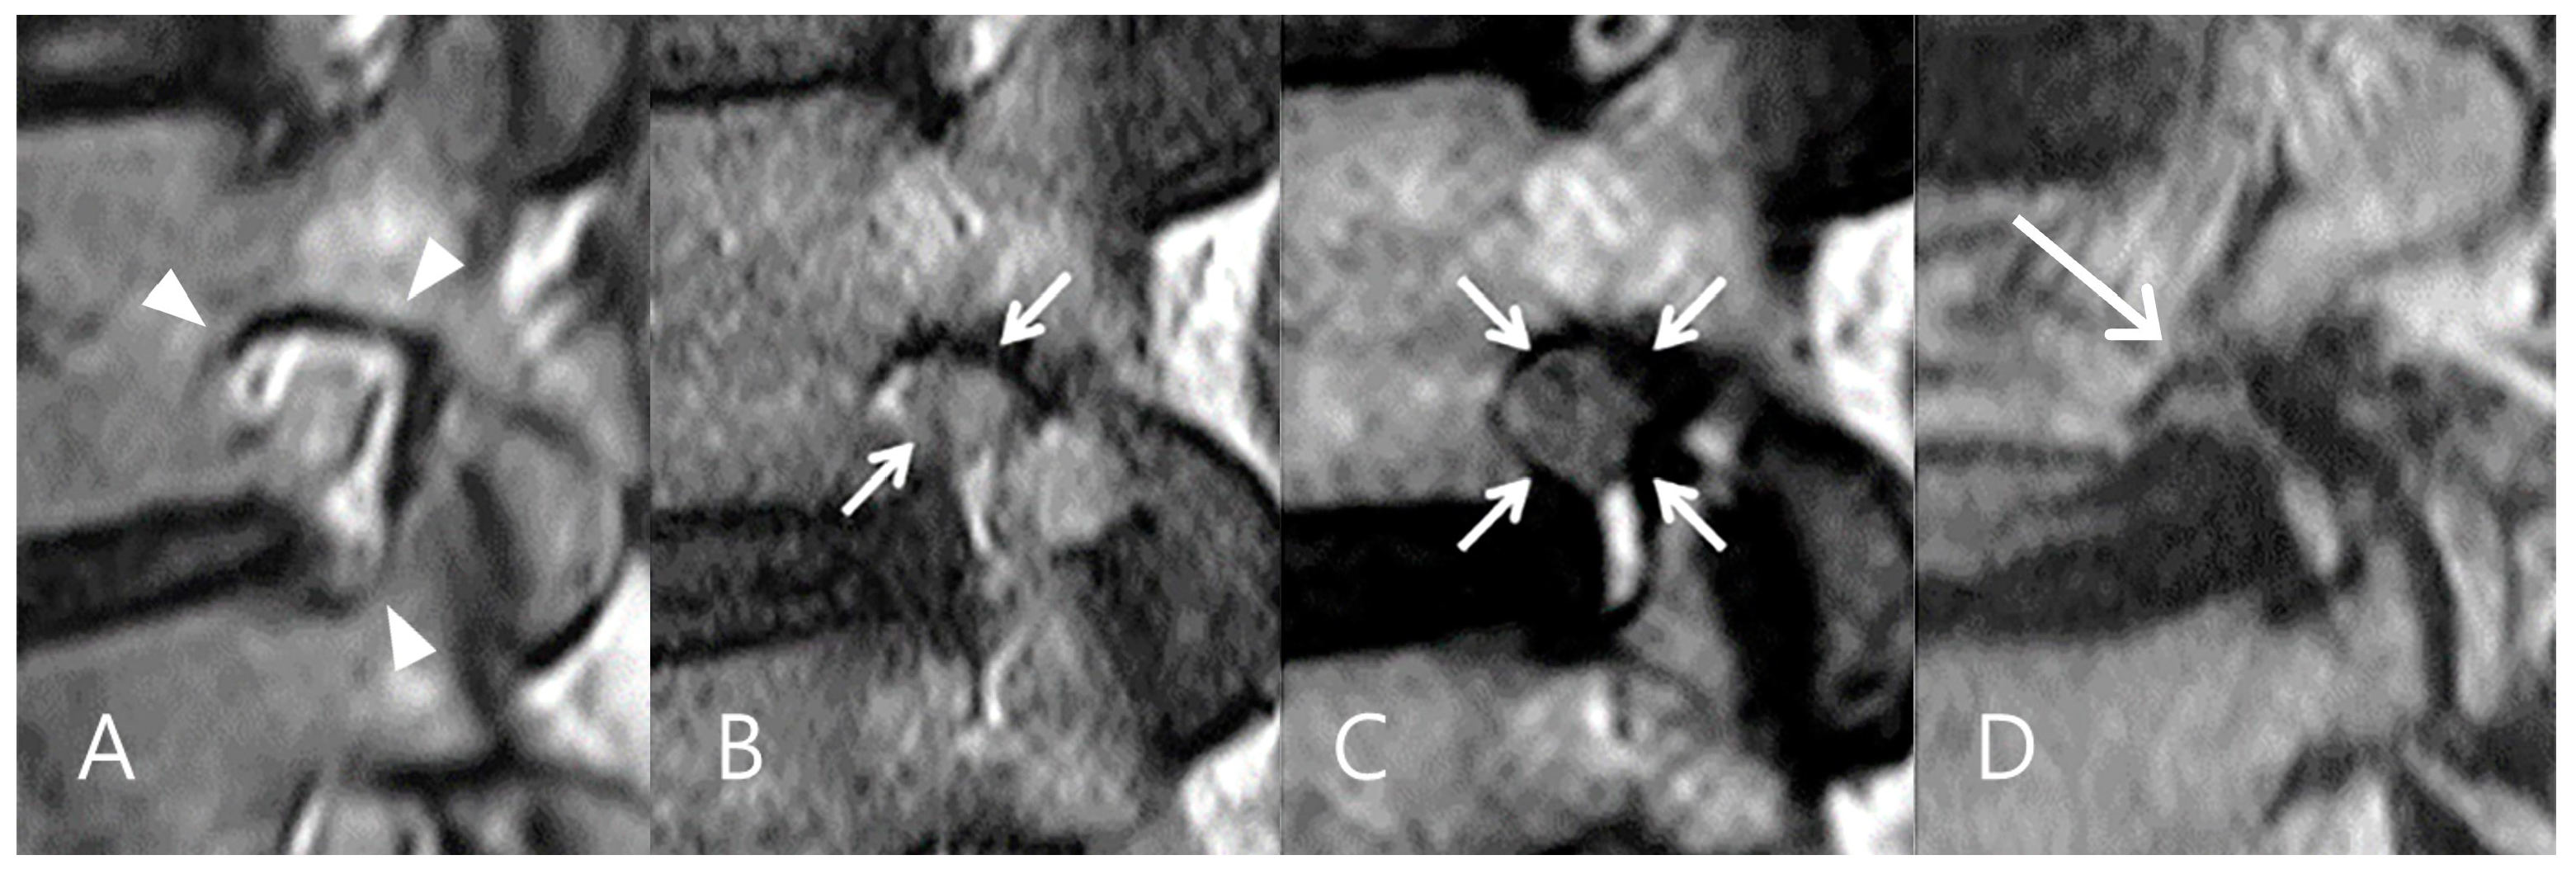

- Lee, S.; Lee, J.W.; Yeom, J.S.; Kim, K.J.; Kim, H.J.; Chung, S.K.; Kang, H.S. A practical MRI grading system for lumbar foraminal stenosis. Am. J. Roentgenol. 2010, 194, 1095–1098. [Google Scholar] [CrossRef]

- Park, H.J.; Kim, S.S.; Lee, S.Y.; Park, N.H.; Rho, M.H.; Hong, H.P.; Kwag, H.J.; Kook, S.H.; Choi, S.H. Clinical correlation of a new MR imaging method for assessing lumbar foraminal stenosis. Am. J. Neuroradiol. 2012, 33, 818–822. [Google Scholar]

- Jeong, T.S.; Ahn, Y.; Lee, S.G.; Kim, W.K.; Son, S.; Kwon, J.H. Correlation between MRI grading system and surgical findings for lumbar foraminal stenosis. J. Korean Neurosurg. Soc. 2017, 60, 465–470. [Google Scholar] [PubMed]